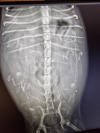

Gestern hat unsere Mona ihr Baby zur Welt gebracht. Ihr wundert euch sicher, dass wir nix gesagt haben. Aber wir waren schon „etwas geschockt“, als unser Frauli gemeinsam mit der TÄ nur eine Fruchtanlage auf dem Ultraschallbild gesehen hat. Deshalb dachten wir uns, warten wir mal das Röntgenbild ab. Aber auch das zeigte keinen weiteren Welpen und der eine sah zudem auch noch sehr groß aus und er lag quer. Deshalb haben wir das nicht „an die große Glocke gehängt“, sondern wollten erstmal abwarten, bis der Zwerg gesund auf der Welt ist. Und das hat Mona zum Glück gestern Abend „geschafft“. Näheres jetzt unter P1-Wurf.